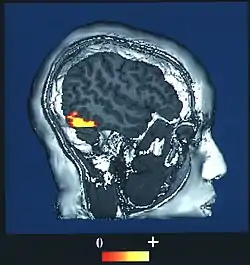

Brain imaging studies typically show a great deal of activity in an area of the temporal lobe known as the fusiform gyrus, an area also known to cause prosopagnosia when damaged (particularly when damage occurs on both sides). This evidence has led to a particular interest in this area and it is sometimes referred to as the fusiform face area (FFA) for that reason.[10]

The fusiform face area (BA37— Brodmann area 37) is located in the lateral fusiform gyrus. It is thought that this area is involved in holistic processing of faces and it is sensitive to the presence of facial parts as well as the configuration of these parts. The fusiform face area is also necessary for successful face detection and identification. This is supported by fMRI activation and studies on prosopagnosia, which involves lesions in the fusiform face area.[34][35][36][37][38]

The occipital face area is located in the inferior occipital gyrus.[35][38] Similar to the fusiform face area, this area is also active during successful face detection and identification, a finding that is supported by fMRI and MEG activation.[34][38] The occipital face area is involved and necessary in the analysis of facial parts but not in the spacing or configuration of facial parts. This suggests that the occipital face area may be involved in a facial processing step that occurs prior to fusiform face area processing.[34][38]

During face perception, major activations occur in the extrastriate areas bilaterally, particularly in the above three areas.[34][35][38] Perceiving an inverted human face involves increased activity in the inferior temporal cortex, while perceiving a misaligned face involves increased activity in the occipital cortex. No results were found when perceiving a dog face, suggesting a process specific to human faces.[41] Bilateral activation is generally shown in all of these specialized facial areas.[42][43][44][45][46][47] However, some studies show increased activation in one side over the other: for instance, the right fusiform gyrus is more important for facial processing in complex situations.[36]